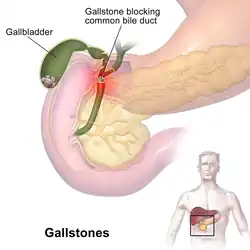

| Gallstones typically form in the gallbladder and may result in symptoms if they block the biliary system. | |

A gallstone is a stone formed within the gallbladder from precipitated bile components.[2] The term cholelithiasis may refer to the presence of gallstones or to any disease caused by gallstones,[5] and choledocholithiasis refers to the presence of migrated gallstones within bile ducts.

Gallstone disease refers to the condition where gallstones are either in the gallbladder or common bile duct.[5] The presence of stones in the gallbladder is referred to as cholelithiasis, from the Greek chole- (χολή, 'bile') + lith- (λίθος, 'stone') + -iasis (ἴασις, 'process').[1] The presence of gallstones in the common bile duct is called choledocholithiasis, from the Greek choledocho- (χοληδόχος, 'bile-containing', from chol- + docho-, 'duct') + lith- + -iasis.[1] Choledocholithiasis is frequently associated with obstruction of the bile ducts, which can lead to cholangitis, from the Greek: chol- + ang- (ἄγγος, 'vessel') + -itis (-ῖτις, 'inflammation'), a serious infection of the bile ducts. Gallstones within the ampulla of Vater can obstruct the exocrine system of the pancreas and can result in pancreatitis.

Choledocholithiasis

Choledocholithiasis refers to a gallstone obstructing the common bile duct.[20] Patients typically experience right upper quadrant pain, back pain, jaundice (or yellowing of the skin), decreased appetite, nausea, vomiting, and fever.[13][20] However, choledocholithiasis, just like gallstones, can also be asymptomatic.[14][21] If the patient has symptoms, the physical exam is similar to that of acute cholecystitis.[20] Laboratory studies show an increase in direct (conjugated) bilirubin, gamma-glutamyl transpeptidase (GGT), and alkaline phosphatase. AST and ALT can be elevated or normal.[14][15][21]